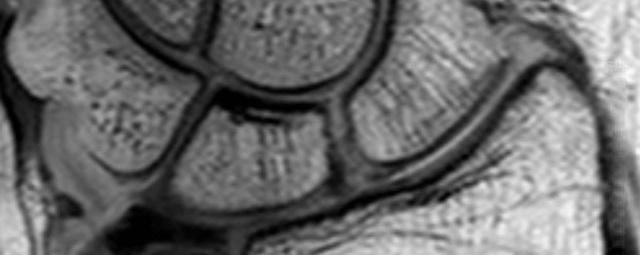

- Beurteilung von Knochen, Bändern und anderen Weichteilstrukturen der Gelenke nach Unfall.

- Arthrosediagnostik (Knorpelschaden)

- Ursachenklärung bei wiederholter spontaner Gelenkluxation

- Ausbreitungsdiagnostik bei Gelenkentzündung, z.B. im Rahmen von rheumatischen Grunderkrankungen

- MR-Arthrographie – nach örtlicher Betäubung und gründlicher Desinfektion der Haut wird unter Lagekontrolle mit Röntgen-Durchleuchtung eine kleine Nadel in den Gelenkraum positoniert und darüber ein MR-taugliches Kontrastmittel in den Gelenkraum gespritzt. Danach wird die Nadel entfernt. Anschließend erfolgt die MRT des Gelenkes. Diese Methode stellt kleine anatomische Strukturen des Gelenkraumes verbessert dar, z.B. zur Therapieplanung vor Arthroskopie bei Sportverletzungen der Schulter oder Gelenkinstabilität.